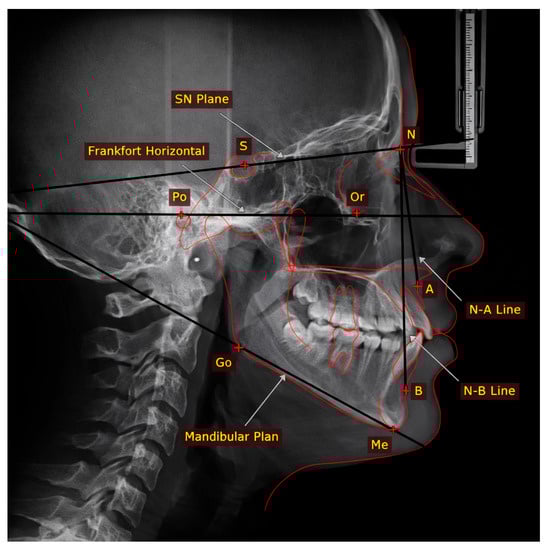

Three-Dimensional Quantitative Analysis of Maxillary Arch Morphology Across Sagittal and Vertical Skeletal Patterns

Background: Contemporary three-dimensional morphometric analysis emphasizes quantitative modeling of anatomical interactions. However, the interplay between sagittal and vertical dimensions in determining maxillary transverse morphology remains inadequately characterized. This study introduces the Sagittal Modulation Effect (SME) framework—a model characterizing how sagittal relationships modify the association between vertical pattern and maxillary arch morphology. Methods: A retrospective cross-sectional analysis was conducted on 165 skeletally mature adults (mean age: 25.4 ± 4.8 years), stratified into skeletal Class I, II, and III groups (n = 55 each). Lateral cephalometric analysis and 3D maxillary digital models were obtained. A validated automated algorithm performed arch morphometric analyses. The primary hypothesis was tested using multiple linear regression with interaction terms, validated via bootstrap analysis and cross-validation. Results: A significant SME was identified (p < 0.001). The inverse correlation between SN-MP and maxillary width intensified progressively: minimal in Class I (r = −0.047, p_adj = 0.891), moderate in Class II (r = −0.387, p_adj_ = 0.024), and strong in Class III (r = −0.645, p_adj_ < 0.001). Regression confirmed significant interaction effects (SN-MP × Class III: β = −0.45, p < 0.001; SN-MP × Class II: β = −0.31, p = 0.003). Exploratory analysis identified cohort-specific statistical descriptors associated with narrower arches: SN-MP > 34.2° in Class III (AUC = 0.84) and SN-MP > 36.5° in Class II (AUC = 0.78). These require external validation. Conclusions: This study provides evidence that sagittal classification modulates the vertical–transverse relationship. The SME framework offers class-specific coefficients and exploratory stratification tools for future research pending multi-center validation. Full article